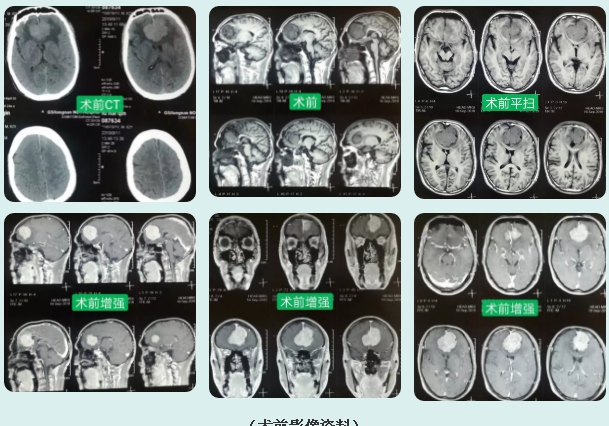

患者符某,男,69岁,主因“突发性抽搐后昏迷6小时”入院,入院后行颅脑CT提示:双侧额叶高密度影,考虑:双侧额叶占位。给予患者对症治疗,第二日神志转清,进一步完善颅脑MRI平扫+增强提示:双侧额叶大脑镰旁脑膜瘤。

(术前影像资料)

完善相关化验及检查,无明显手术禁忌症,决定为患者实施巨大脑膜瘤切除术,术程顺利,术后患者清醒,查体:神志清,精神一般,各项生命体征平稳,语言、视物清晰,对答切题,四肢肌力正常,生理反射存在,病理反射未引出。